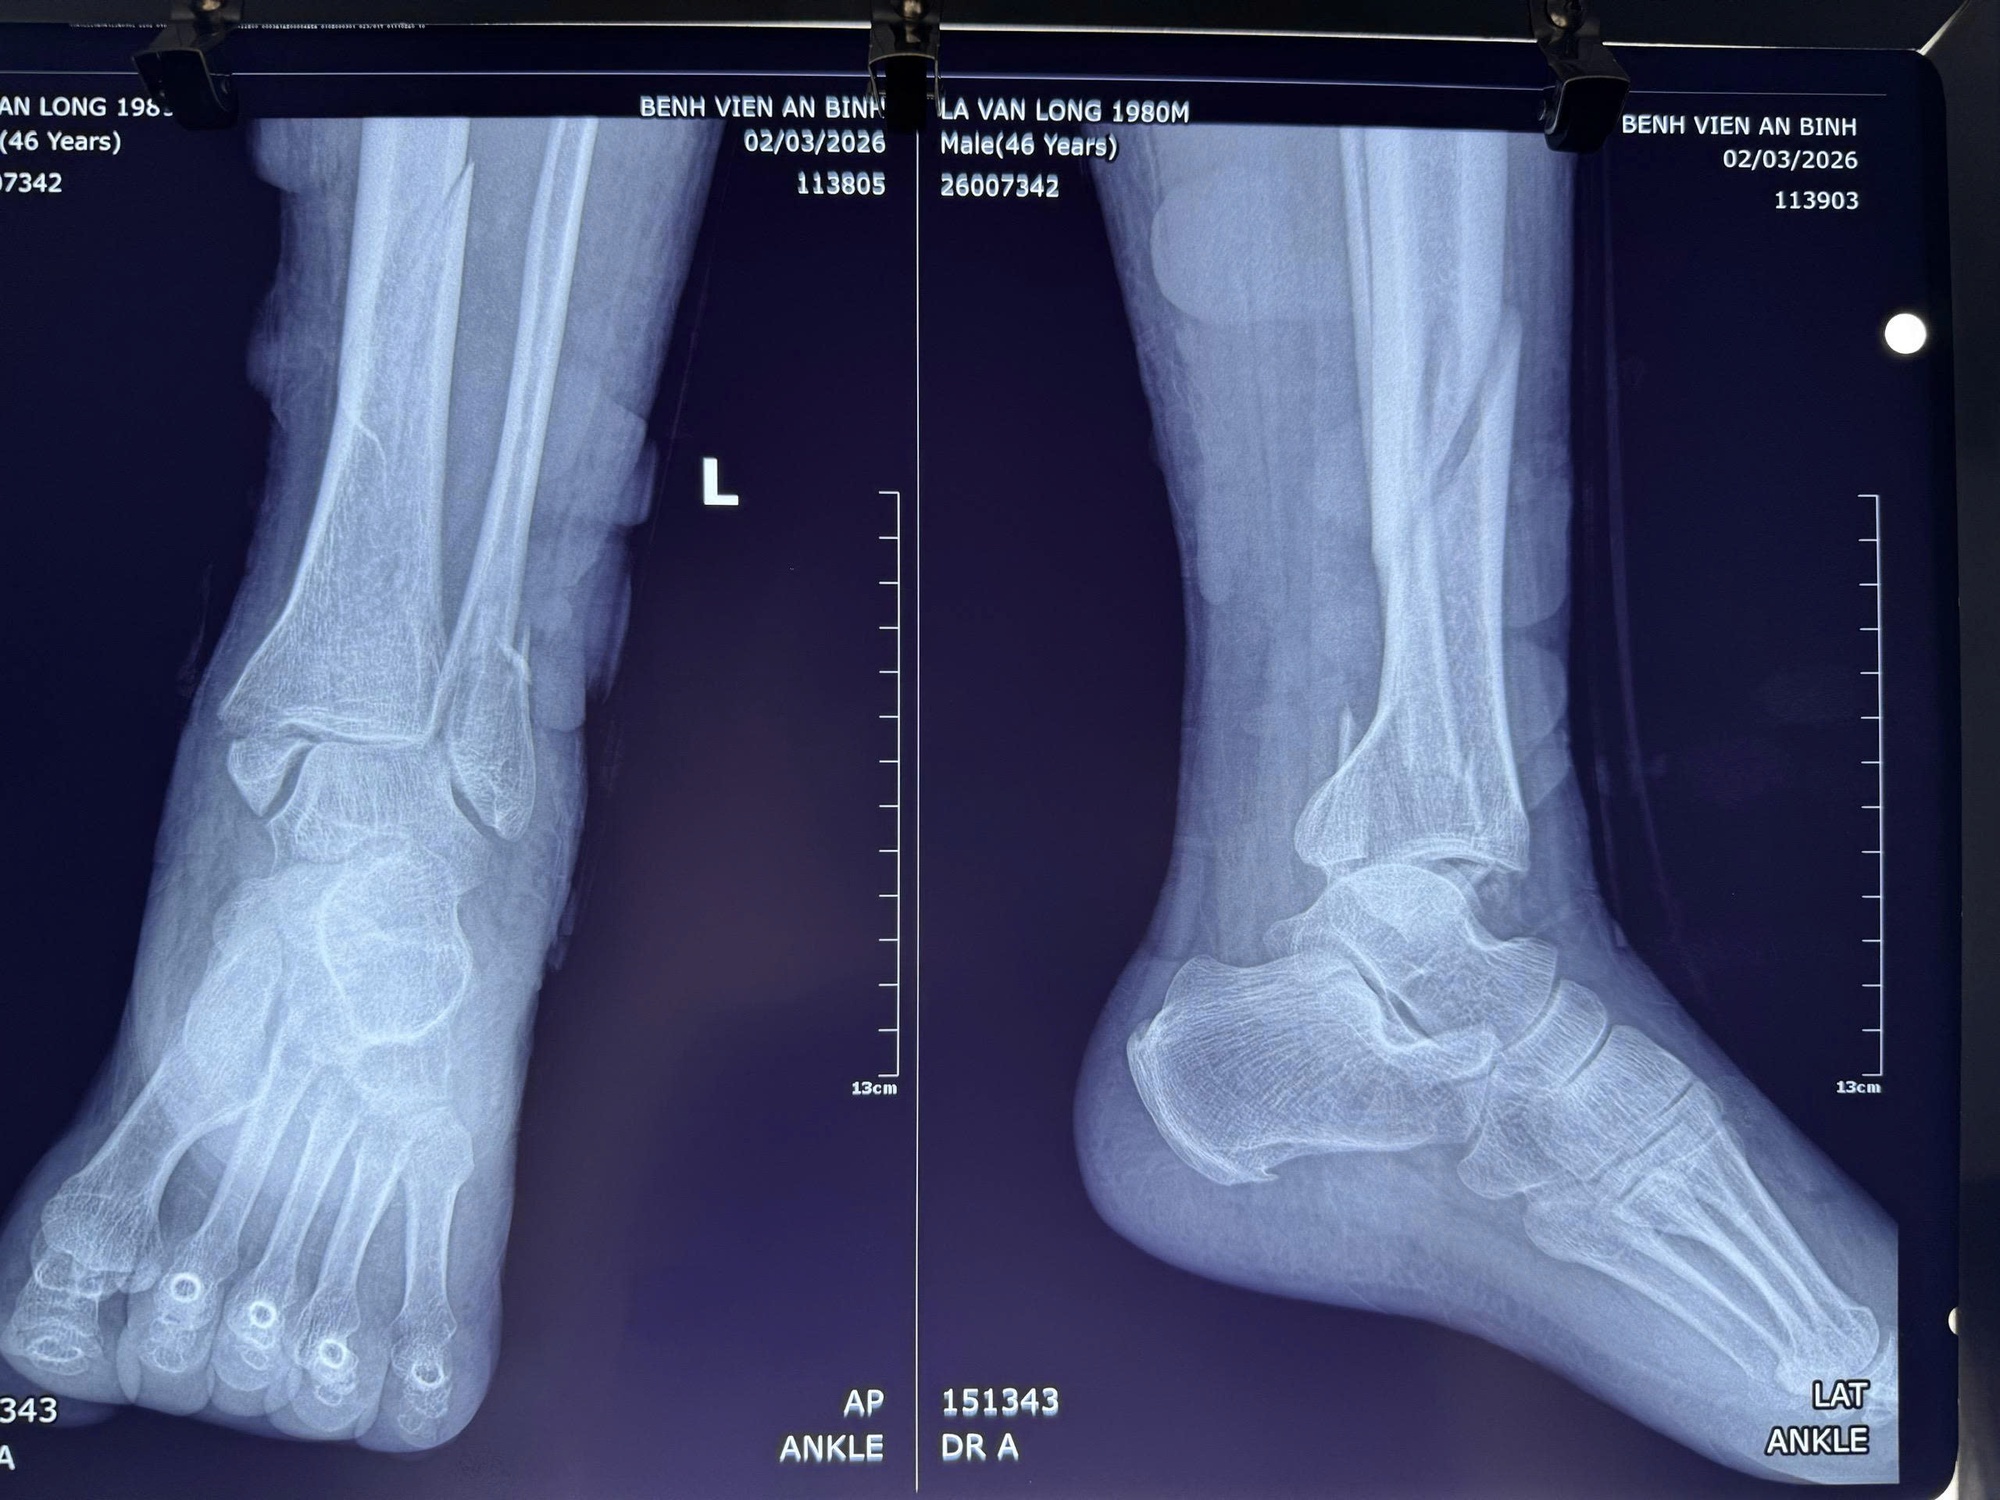

Chụp X-quang cho thấy gãy phức tạp ba mắt cá, bán trật khớp cổ chân kèm gãy 1/3 dưới xương chày

Những ngày đầu, bệnh nhân nghĩ rằng chỉ cần đắp thuốc vài hôm là khỏi. Nhưng chỉ sau 2 ngày, chân bắt đầu sưng to, nổi nhiều bọng nước, đau dữ dội và biến dạng cổ chân. Khi không thể chịu nổi cơn đau, bệnh nhân mới đến bệnh viện. Sau khi kiểm tra, bệnh nhân bị gãy phức tạp 3 mắt cá chân, gãy 1/3 dưới xương chày, bán trật khớp cổ chân, rối loạn dinh dưỡng mô mềm và viêm mô bào cẳng bàn chân trái.